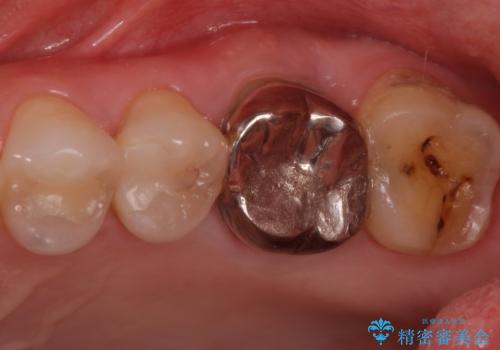

検査で見つかった虫歯 セラミッククラウンでの治療

担当医 岡田康成